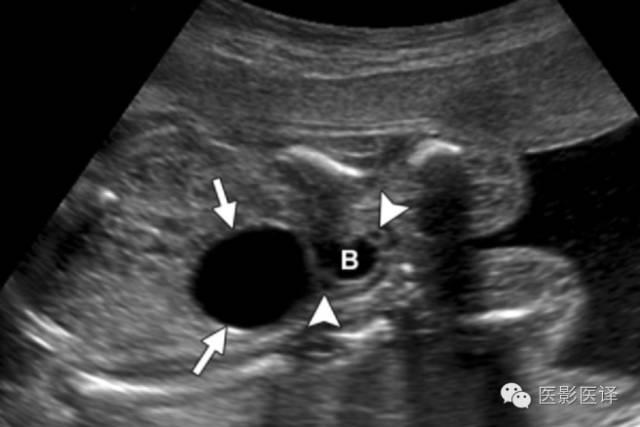

Nussbaum等最早将新生儿卵巢囊肿分为单纯性和复杂性。单纯性卵巢囊肿是圆的、无回声的、单房和薄壁的(图1)。它们更经常为单侧而非双侧、更经常为腹内而非盆腔内。单纯性囊肿内偶尔可见单个分隔(图2)。直径小于20mm的卵巢囊性结构被认为是成熟卵泡,为生理性而非病理性。直径大于20mm的囊肿则考虑为异常。“子囊”征描述的是囊内一个小的、圆形、无回声结构(图3)。既往报道认为这是卵巢囊肿的特征。【在一个23例囊性病变的研究中(包括新生儿、婴儿及儿童),11例发现子囊,占卵巢囊肿的82%(敏感度82%,特异度100%,阳性预测值100%),在其他囊性病变中未发现子囊,包括淋巴管瘤、肠重复畸形、肠囊肿、胎粪假性囊肿、阴道积液和脐尿管囊肿。】

图1:单纯性卵巢囊肿。冠状位胎儿超声图像显示一个边界清楚的薄壁无回声囊肿(箭),高于膀胱(B)位于腹内中线之外。注意脐动脉(箭头)在膀胱两侧。